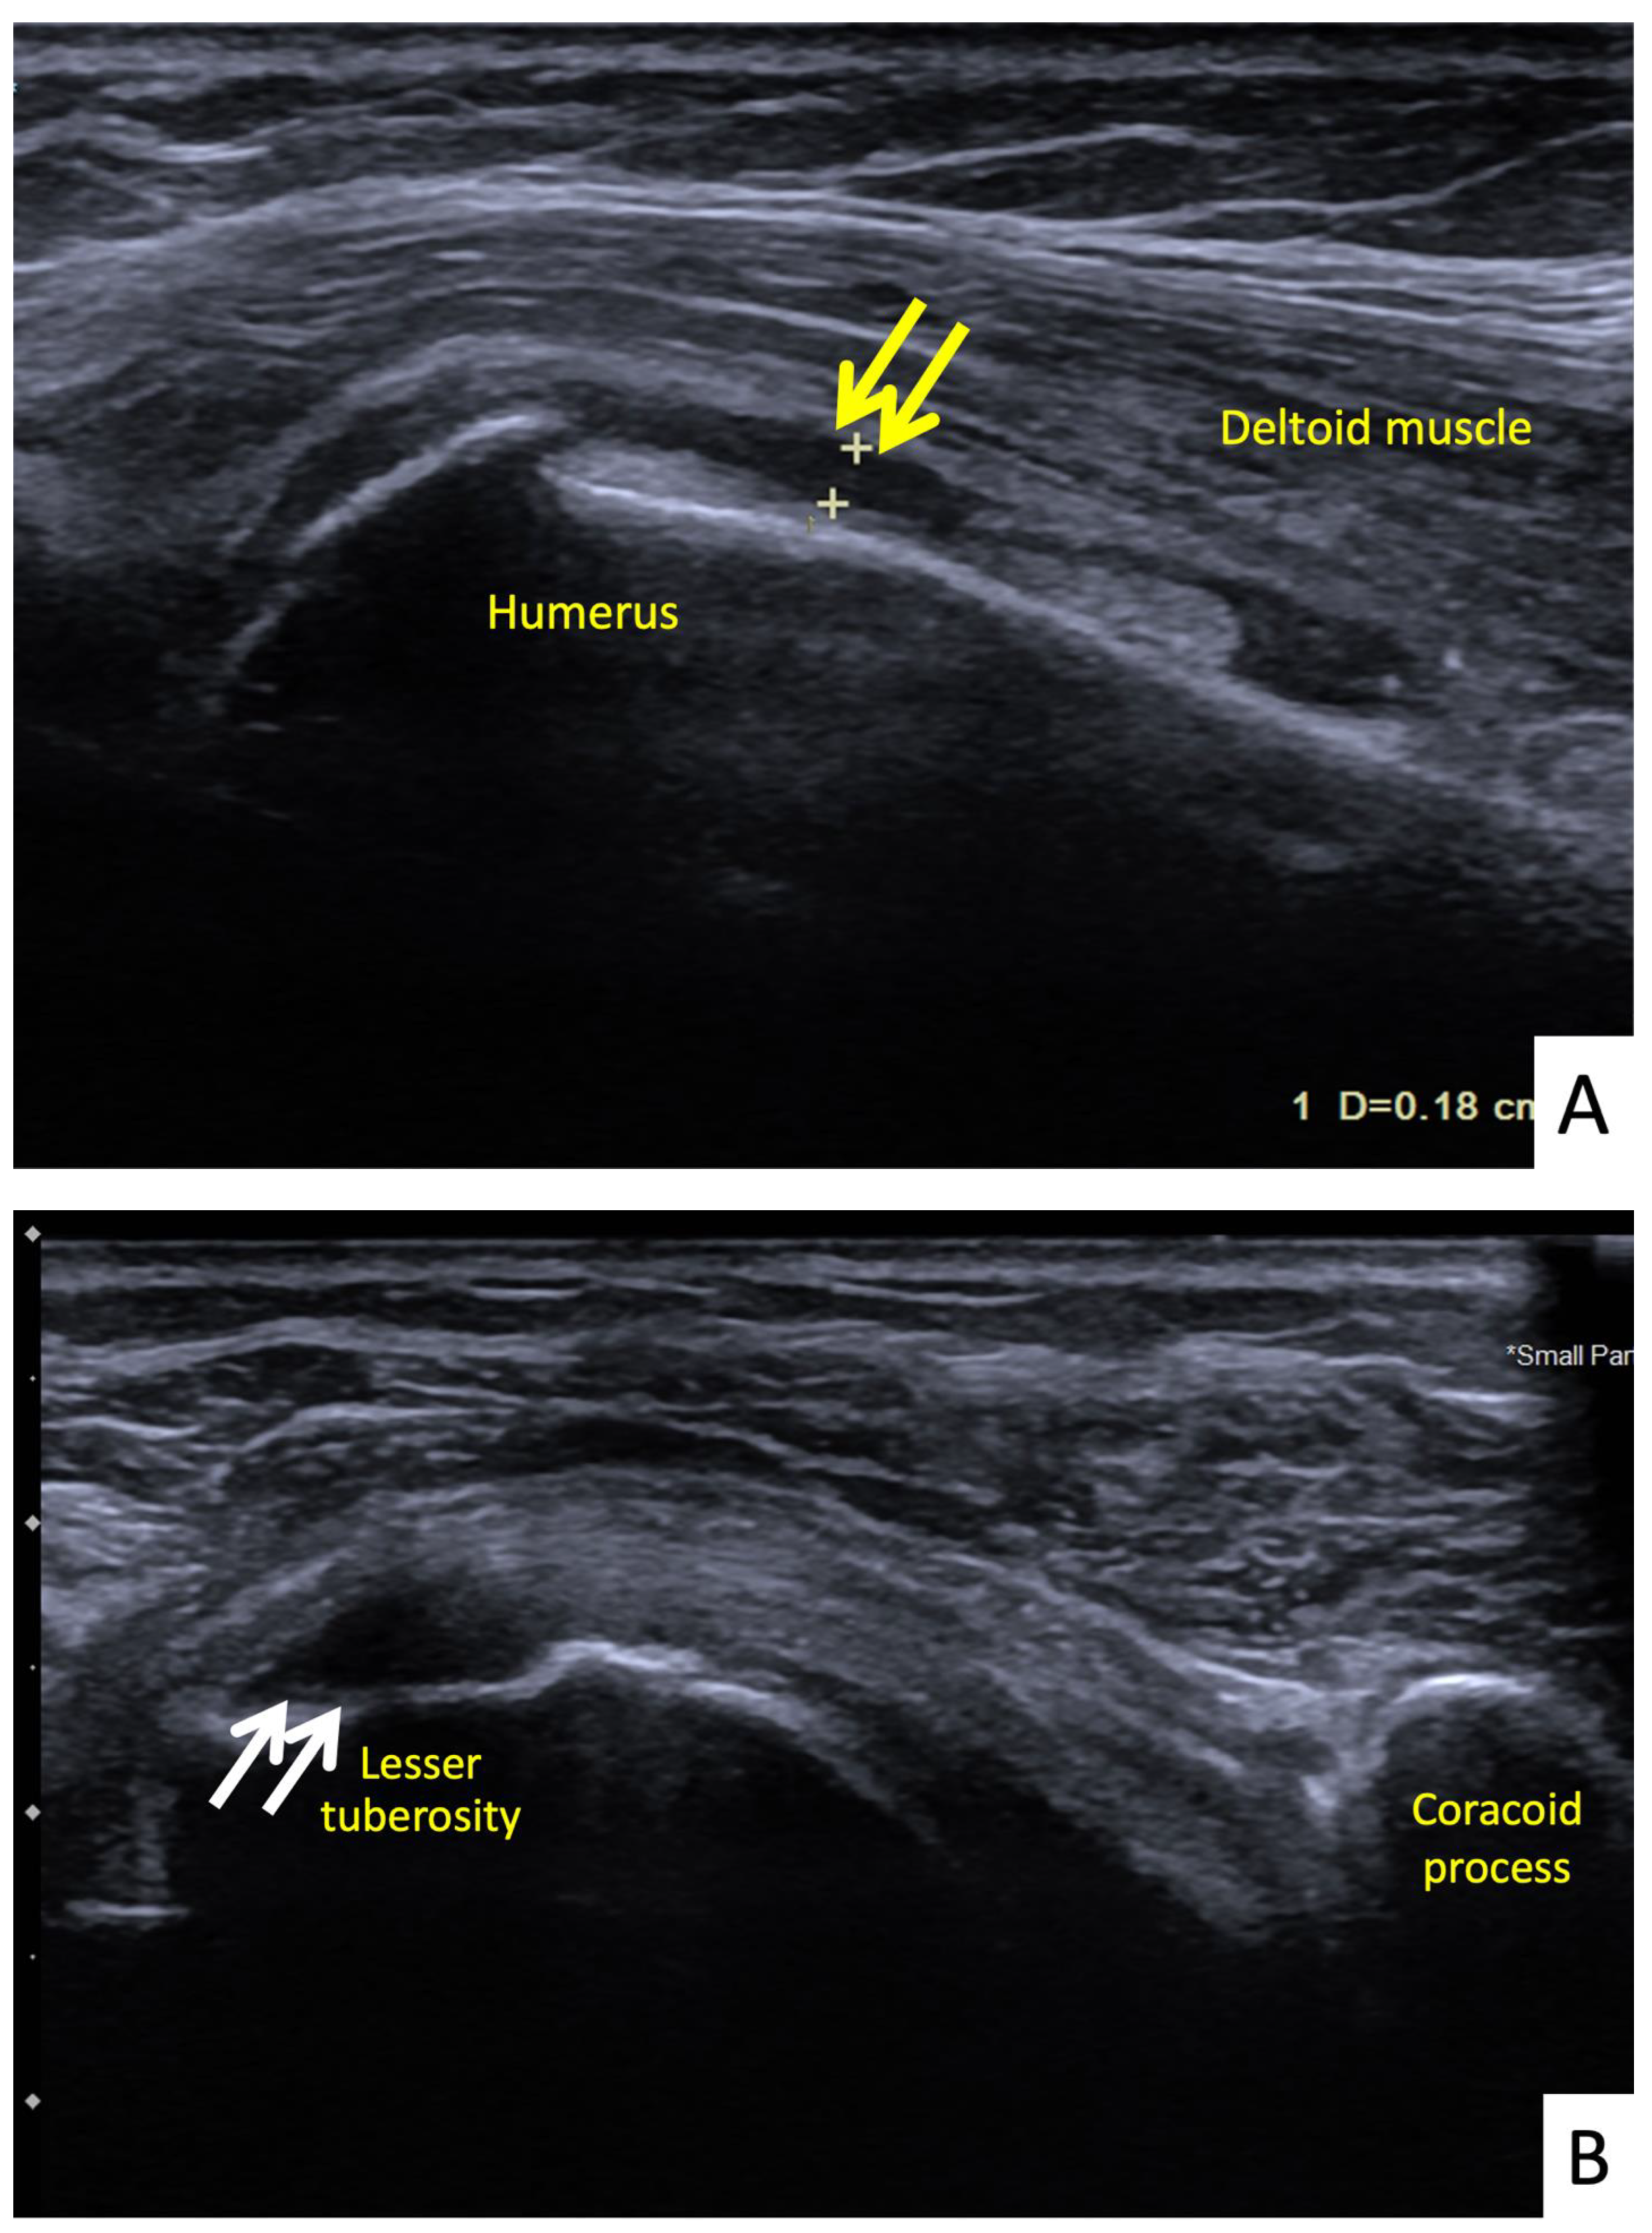

Figure 6.

Ultrasonographic images of the right shoulder of Patient 5. (A) A longitudinal ultrasonographic image over the lateral aspect of the left proximal humerus with the patient in supination showing a small amount of fluid (yellow arrows) in the mildly distended subdeltoid bursa. (B) A transverse ultrasonographic image over the lesser tuberosity of the right shoulder with the patient in the external rotation position showing a partial thickness, articular surface tear at the footprint of the subscapularis tendon (white arrows).

The sixth case was a 64-year-old Thai male who had received his first dose of AstraZeneca vaccine. The vaccination landmark was 3 fingerbreadths below the acromial process with a needle direction of 30 degrees cephalad to the skin. He had developed right shoulder pain with limited range of motion in all directions within 48 h of receiving the vaccine. He did not take any medications, and when the symptoms had not improved in a month he decided to see an orthopedist. A physical examination showed tenderness at the deltoid muscle with limited range of motion in all directions. An ultrasonography showed tenosynovitis at the long head of the biceps and a low-grade partial tear of the subscapularis tendon (Figure 7A,B). He was treated with oral prednisolone (30 mg/day) for 5 days and an intraarticular steroid injection (triamcinolone acetate (TA) 40 mg/mL). His shoulder pain gradually improved, and he could return to normal activities within 7 days after treatment.

Figure 7.

Ultrasonographic images of the right shoulder of Patient 6. (A) A transverse ultrasonographic image over the lesser tuberosity of the right shoulder with the patient in the external rotation position showing a small, partial thickness, intrasubstance tear (yellow arrow) at the footprint of the subscapularis tendon. (B) A transverse ultrasonographic image over the bicipital groove with the patient placing his hand palm up in supination on his leg showing surrounding fluid (white arrow) within the long head biceps tendon sheath, indicating tenosynovitis.